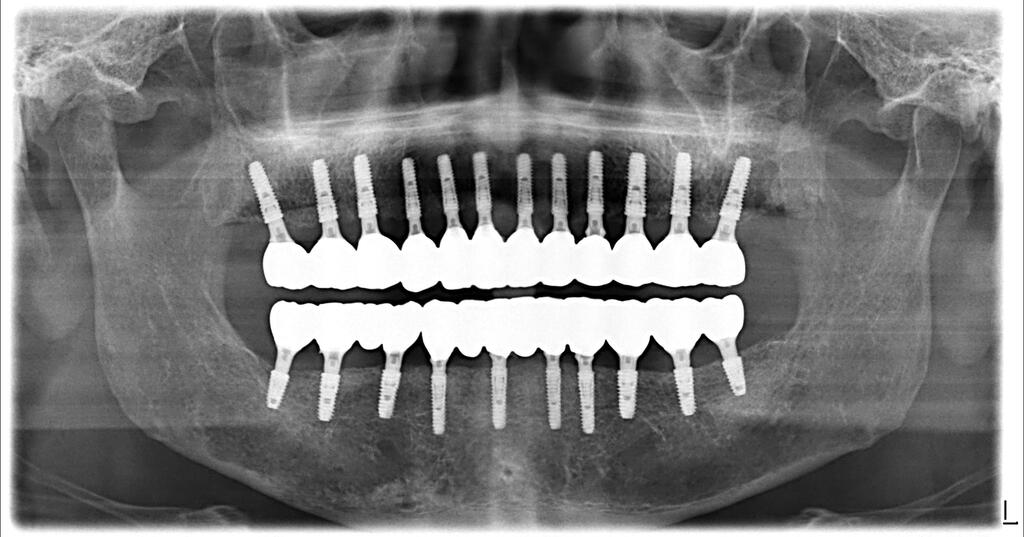

그렇게 해서 2000년도부터 즉시하중 전체임플란트 치료를 시작하게 됩니다. 지금도 즉시하중을 하시는 분들이 그리 많지 않지만 그때에는 정말 획기적인 치료방법이었습니다.

지난 30년간의 임상을 정리해 보니 2025년 9월 기준, 누적 임플란트 식립 90,696건을 달성했고, 전체임플란트 사례는 3천명이 넘어섰습니다.